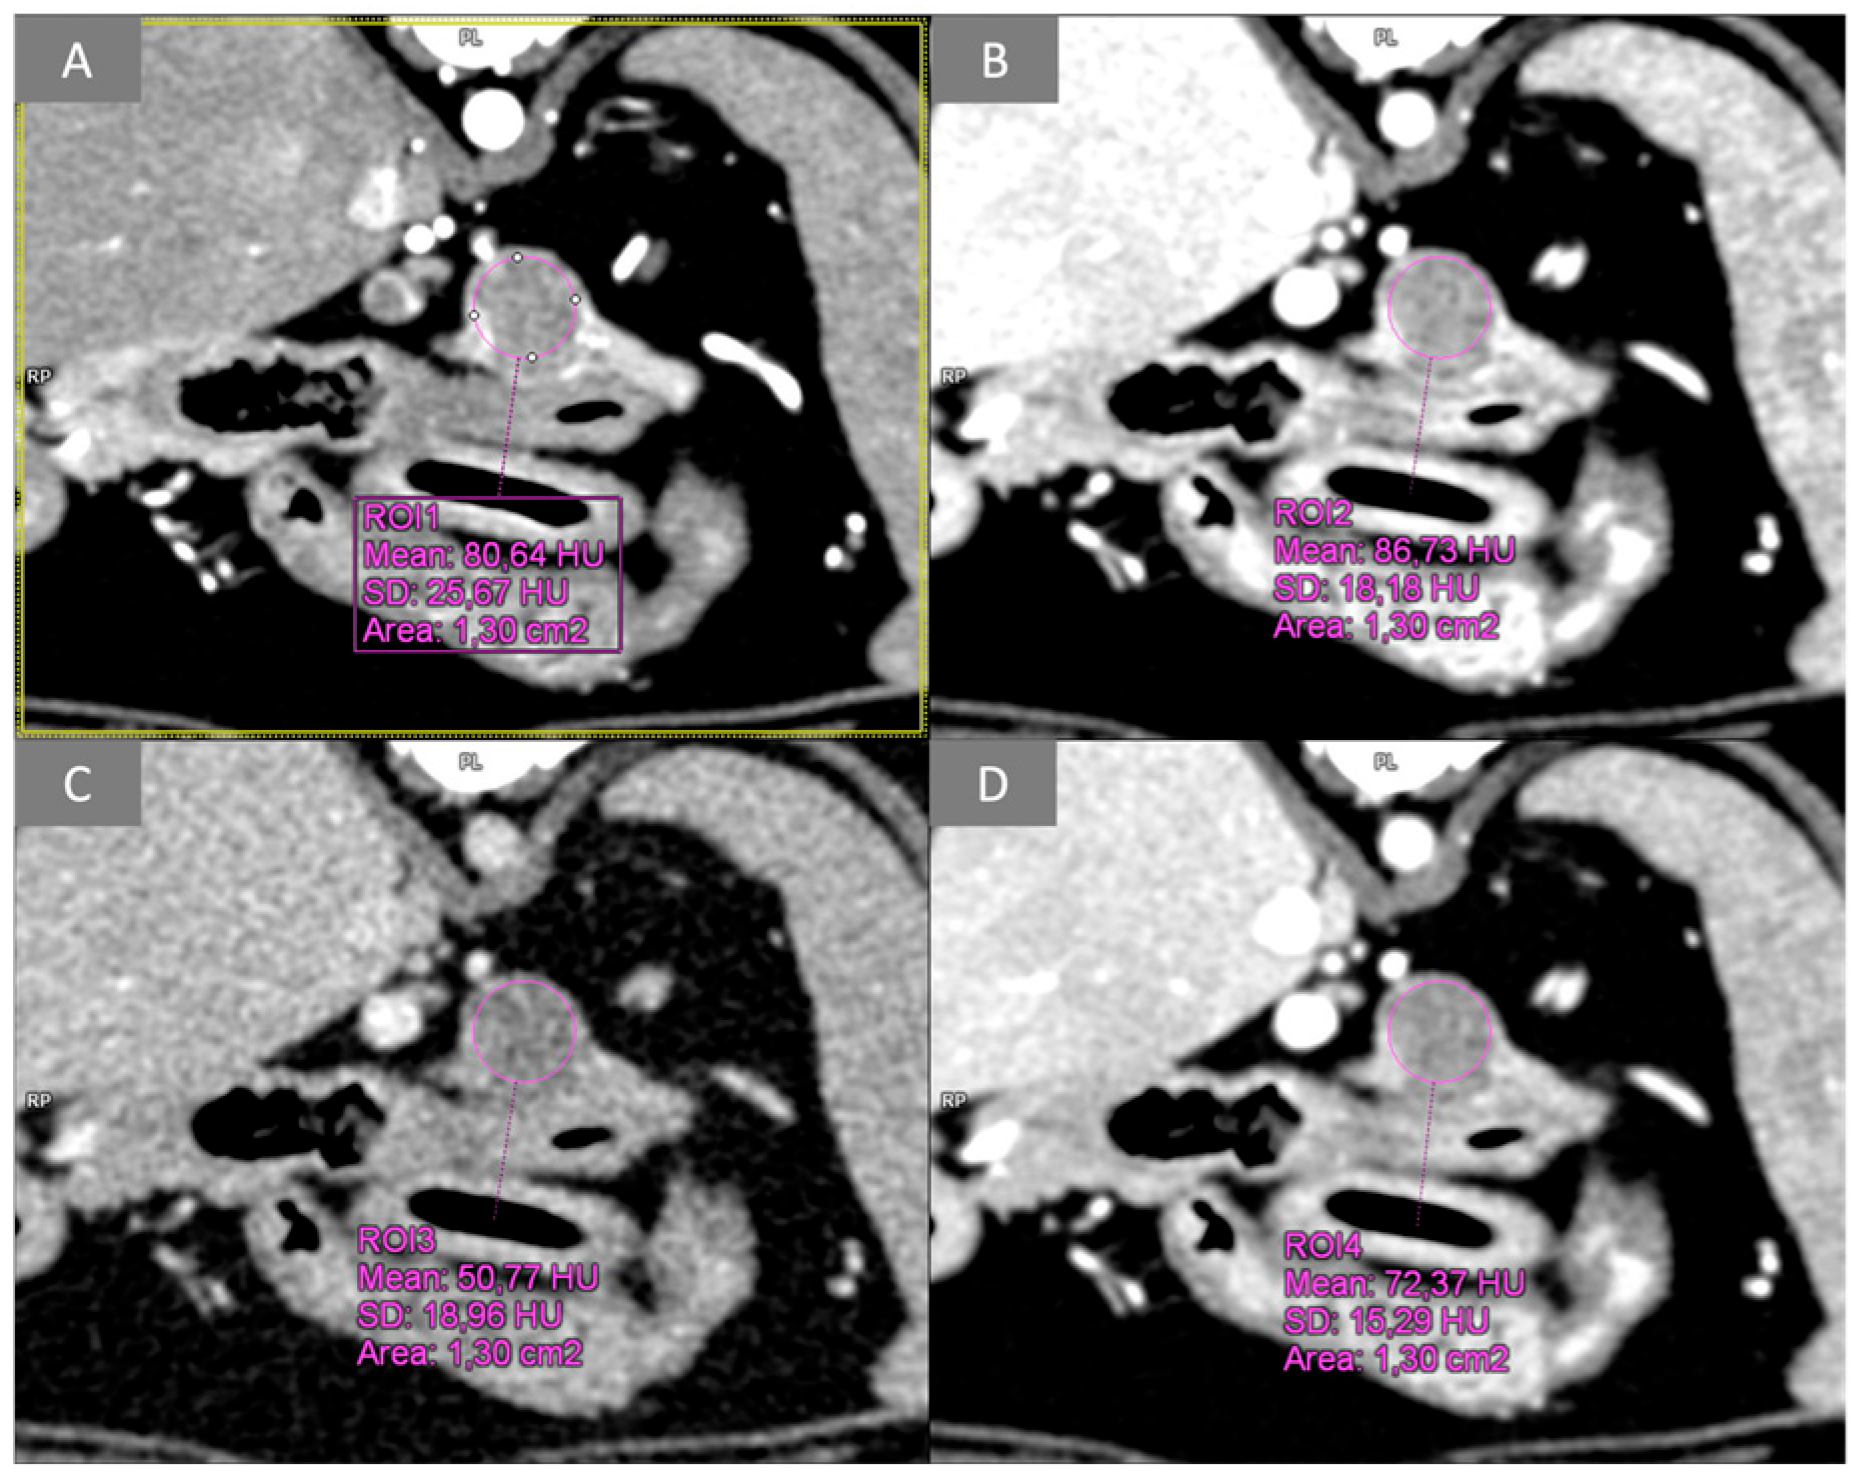

2.3.1. Quantitative Analysis

3.2. Quantitative Analysis